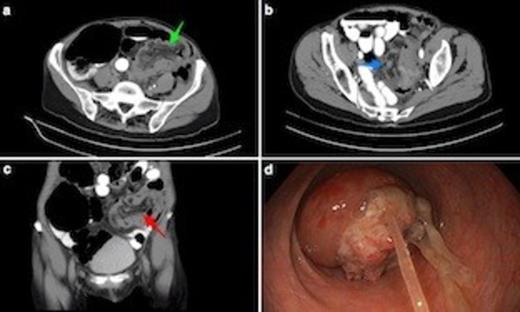

(a) Axial CT scan shows sigmoidorectal intussusception. Note bowel wall thickening. Low attenuation mesenteric tissue is drawn into intussusceptum, with associated caecal dilatation. (b) Axial view through mid-pelvis showing gas between bowel wall of intussusceptum and intussucipiens (i.e. sigmoid colon and rectum: this does not represent intramural gas). (c) Coronal view demonstrating mesenteric vasculature in the intussusceptum. (d) Endoscopic view from mid rectum of tumour intussusception. The underlying lesion was an apple core T3N1 adenocarcinoma of the mid-sigmoid. Note tumour mucus.

Subsequent CT scan revealed a rounded heterogeneous density protruding into the lumen of the upper rectum containing mesenteric fat and blood vessels (Figs. 1a-c). The appearance was suggestive of sigmoidorectal intussusception. There was significant associated proximal large bowel dilatation consistent with left-sided colonic obstruction.